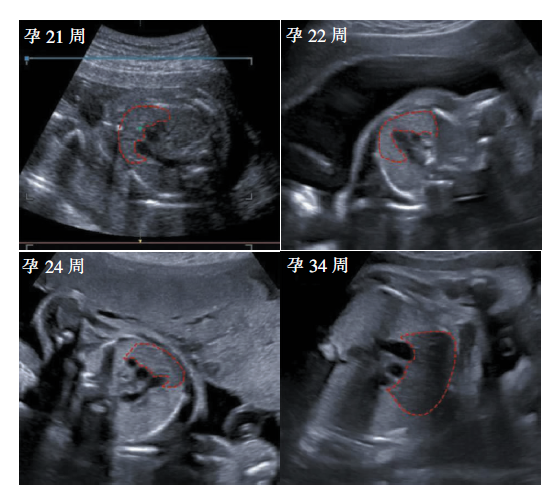

YANG Tian, JI Xiang, NIU Jianmei, KONG Xiaoxiao, LV Mingli. Application of 2D-ultrasonography in prenatal assessment of fetal thymus development[J]. Journal of Diagnostics Concepts & Practice, 2021, 20(05): 471-474.